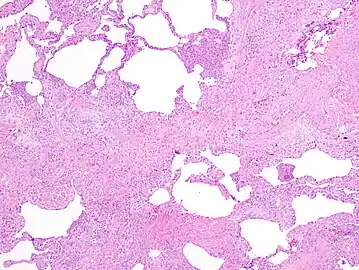

The histologic hallmarks of UIP, as seen in lung tissue under a microscope by a pathologist, are interstitial fibrosis in a "patchwork pattern", honeycomb change and fibroblast foci (see images below).[6] [7]

Appearance of honeycomb change in a surgical lung biopsy at low magnification. The dilated spaces seen here are filled with mucin. Hematoxylin-eosin stain, low magnification.